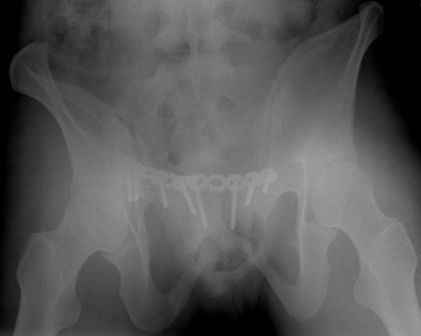

Серия до- и послеоперационных снимков этой пациентки. Хотя бы post factum обсудить. Не знаю, что можно сделать с задними отделами стержневым аппаратом, но три крепких парня открытым путем с помощью "волшебных" слов еле-еле смогли отрепонировать - сзади все было очень ригидно!